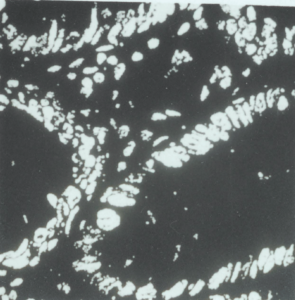

5:3. The processed images generated by the image cytometer.

5:4. Comparison of manual and image processed labelling indices.